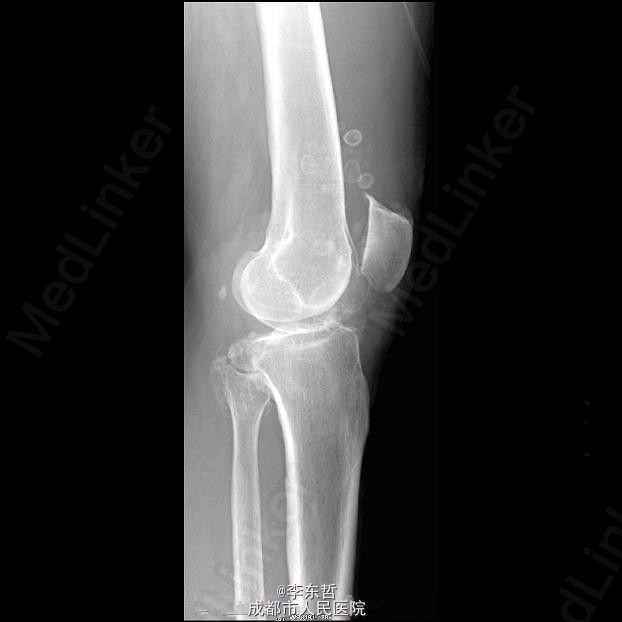

滑膜骨软骨瘤病

患者男性,43岁,自述关节疼痛、肿胀和活动受限数年,偶可触及游离体,常出现关节交锁;